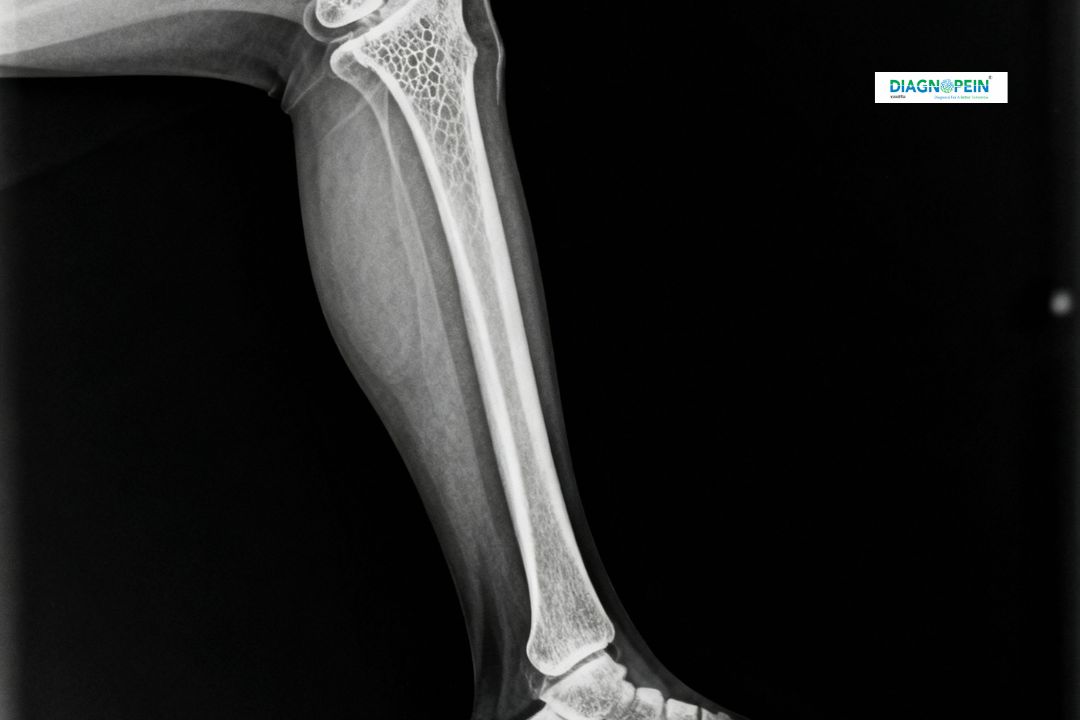

An X-Ray Left Leg AP/LAT is a fundamental diagnostic imaging test that captures detailed anterior-posterior (AP) and lateral (LAT) views of the left leg. This test helps doctors visualize bones, joints, and surrounding tissues to detect fractures, bone deformities, inflammation, or infections. At Diagnopein in Karad, we use advanced digital X-ray equipment to ensure high-precision imaging for accurate clinical interpretation.

A Left Leg AP/LAT X-ray is crucial in diagnosing orthopedic and traumatic injuries. The test provides a clear dual-angle view, allowing the radiologist to evaluate bone alignment, joint space, and tissue health. At Diagnopein, our expert technicians in Karad follow strict safety and radiation protocols to ensure patient comfort and safety during each scan.

The X-Ray Left Leg AP/LAT focuses on analyzing:

1. Bone alignment and continuity

2. Joint spaces (knee and ankle)

3. Presence of bone lesions or fractures

4. Soft tissue abnormalities

5. Postoperative bone fixation (if any)

Each X-ray is interpreted by qualified radiologists at Diagnopein Karad, ensuring diagnostic accuracy and early detection of underlying orthopedic issues.